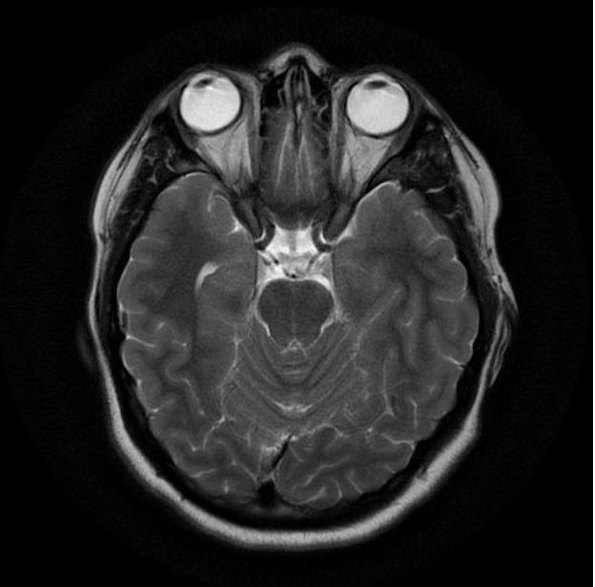

Если вы не знакомы с этим тестом, МРТ использует магнитное поле и радиоволны, чтобы сделать подробные снимки ваших внутренностей.

По данным клиники Мэйо, когда вы находитесь внутри аппарата МРТ, его магнитное поле временно перестраивает атомы водорода в вашем теле. Радиоволны заставляют эти атомы создавать очень слабые сигналы, которые используются для создания изображений поперечного сечения.Эти изображения накладываются друг на друга, чтобы врачам было действительно хорошо видно ваше тело изнутри, которое они могут видеть под разными углами.

«Он обеспечивает отличную анатомическую детализацию мягких тканей, что полезно для оценки конкретных условий», — объясняет она.

По данным клиники Майо, МРТ позволяет выявить широкий спектр проблем, включая аномалии дисков в позвоночнике, проблемы с суставами, опухоли в различных органах, таких как почки и яичники, структурные проблемы в сердце и травмы головного мозга.

Аппарат обычно будет длинным и иметь форму трубки с одним или двумя открытыми концами, хотя более новые «открытые» аппараты МРТ могут не закрываться по бокам. Специалист по МРТ попросит вас лечь на стол и часто протягивает вам гарнитуру, чтобы надеть ее до начала самого теста. «Пациентам выдают гарнитуры, чтобы они могли общаться во время МРТ», — объясняет доктор Таули.

Когда придет время начинать ваш тест, техник войдет за перегородку, и платформа, на которой вы лежите, переместится в аппарат МРТ.Стол, за которым вы сидите, может перемещать вас, чтобы улучшить визуализацию, но обычно вам нужно сохранять как можно более неподвижное тело во время экзамена.

«Очень важно лежать неподвижно во время МРТ-обследования, поскольку любое движение может нарушить формируемые изображения, и обследование необходимо будет повторить», — говорит доктор Макари. Единственное исключение — во время функциональной МРТ, когда техник может попросить вас выполнить небольшие задачи, например, постучать большим пальцем по пальцам, чтобы увидеть, как работает ваш мозг, согласно клинике Майо.